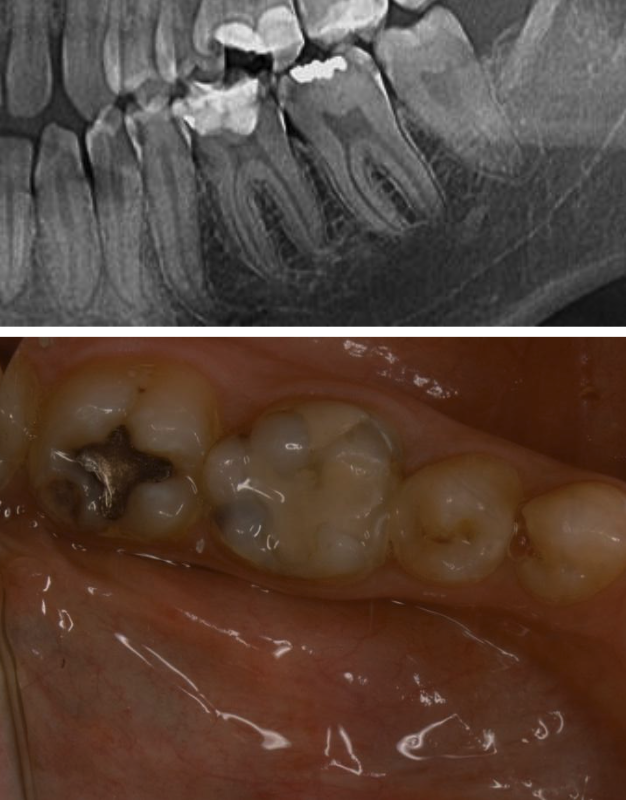

Pacientul s-a prezentat în cadrul clinicii MB Dental Mureș în vederea tratării unei sensibilități localizate în partea inferioară stângă. Examinarea inițială împreună cu cea imagistică ne indică un diagnostic de carie secundară extinsă pe mai multe suprafețe la nivelul molarilor 3.6, 3.7, alături de alte leziuni carioase de extindere mai redusă localizate la nivelul premolarilor si ultimului molar. (Fig. 1)